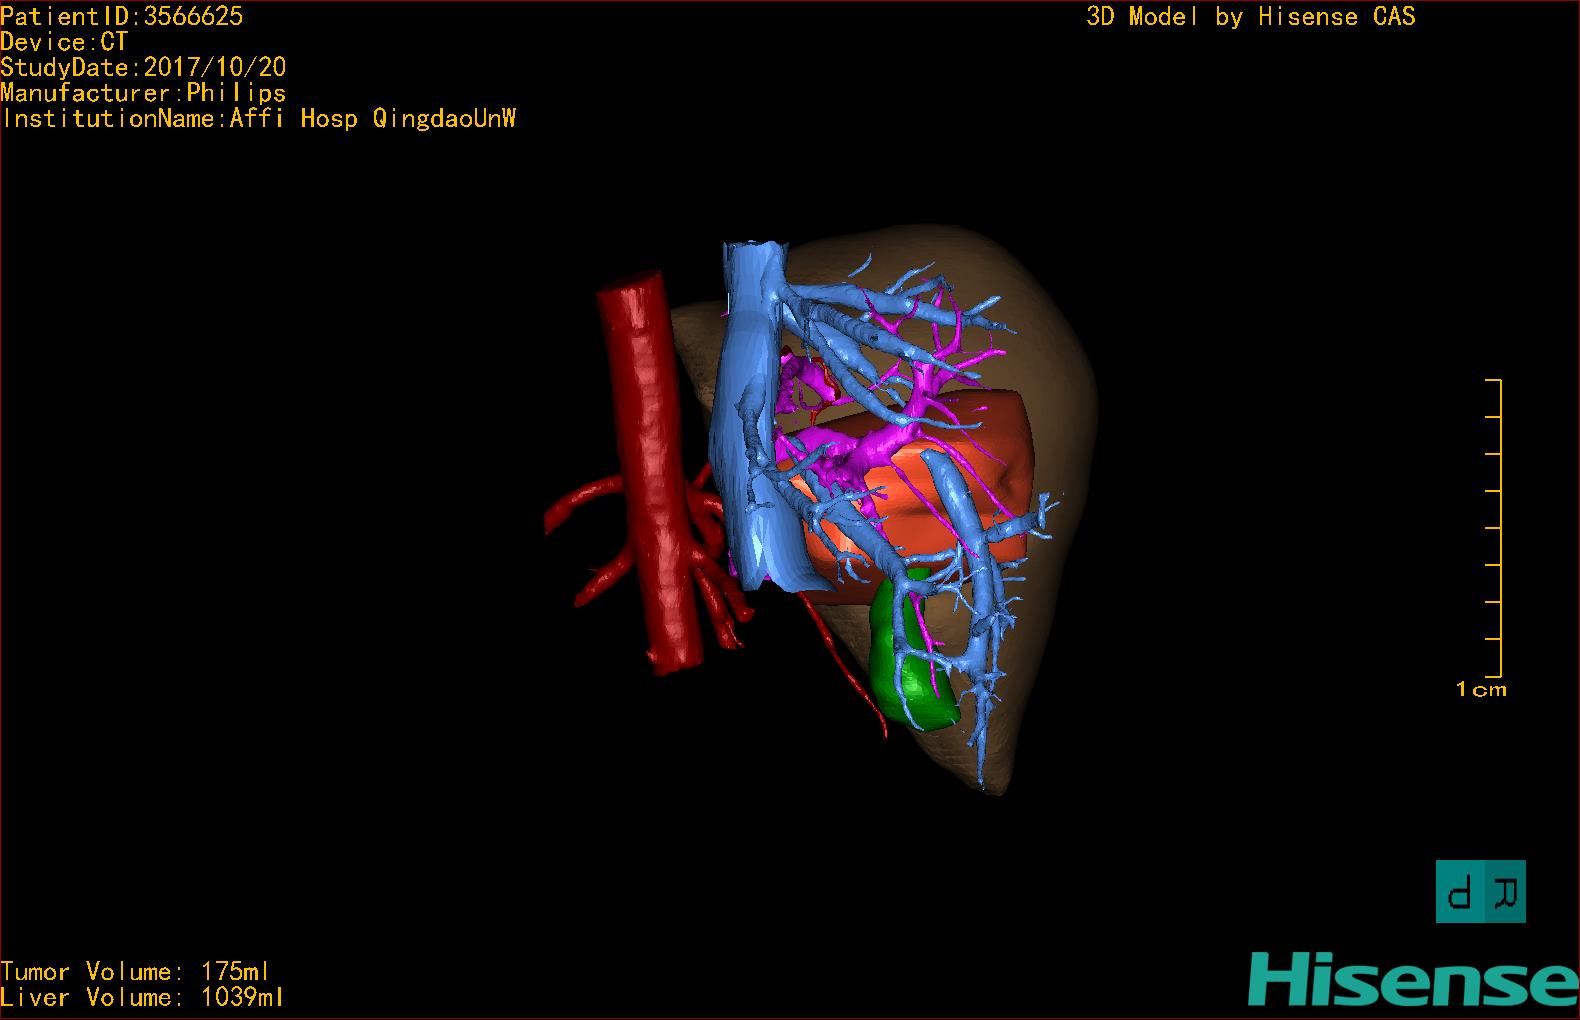

通过调节窗宽窗位调整CT序号,对肿瘤,肝实质,胆囊,下腔静脉,肿瘤,肝动脉、门静脉及肝静脉等进行三维重建;系统自动计算肿瘤体积和肝脏体积。模拟手术操作,自动计算切除肿瘤体积。肝脏体积为1039ml,肿瘤体积为175ml,通过比对40-50岁正常肝脏体积为1423.76±216.93ml,通过术前模拟手术,精准判断切除后剩余肝脏体积能耐受,避免肝衰竭发生。

术前三维重建:

重建图片